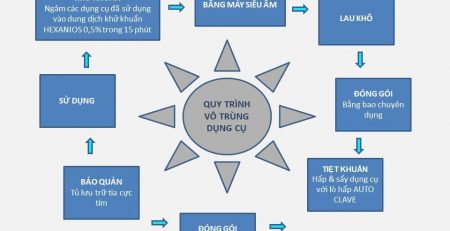

Việc xử lý răng khôn bị sâu không phải đơn giản, nếu thực hiện ở cơ sở vệ sinh kém có thể bị nhiễm trùng. Nhiễm trùng hậu phẫu là một biến chứng khi nhổ răng số 8 diễn ra khá phổ biến.

Tình trạng này nếu không được khắc phục dễ dẫn đến biến chứng hoại tử, nhiễm trùng máu. Vì thế, hãy chọn Trung tâm nha Khoa Aquacare với Quy trình nhổ răng khôn theo tiêu chuẩn quốc tế, luôn đảm bảo chất lượng và sức khỏe cho mỗi khách hàng.